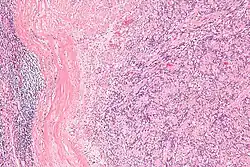

Micrograph of an intranodal palisaded myofibroblastoma. H&E stain.

IPMs are diagnosed by examination of the tissue by a pathologist. They have a rim of peripheral lymphoid tissue (remnant of a lymph node) and consist of spindle cells with nuclear palisading. Red blood cell extravasation is common and blood vessels surrounded by collagen with (fine) peripheral spokes (amianthoid fibers) are usually seen.[2]

Immunostains for smooth muscle actin and cyclin D1 are characteristically positive. The main histologic differential diagnosis is schwannoma.